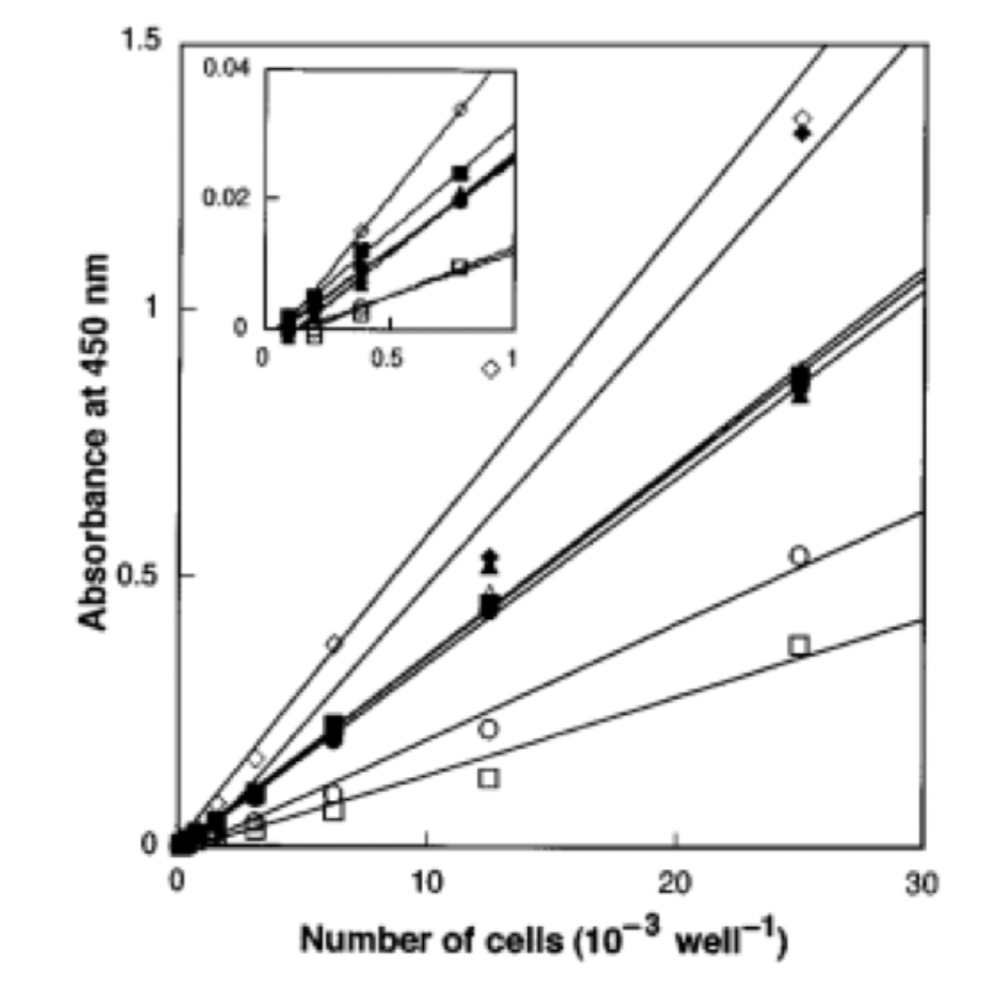

Input 2: Is absorbance related to number of cells?

Image: